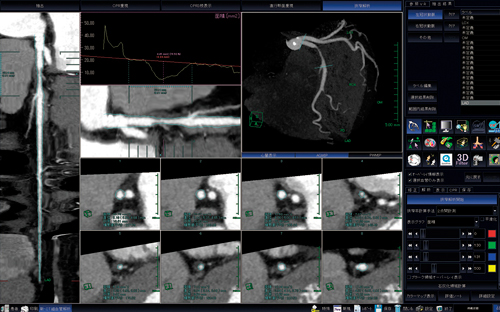

“新・CT細血管解析”は,冠動脈CTの解析ソフトウェアであり,冠動脈CT画像の読み込みと同時に左右冠動脈,大動脈,心臓(心筋)などに自動セグメンテーションされる(図1)。セグメンテーションされた各冠動脈に対して,中心線の修正と名前付けをすると,あとは画像をAngiographic ViewやCPR(図2),直交断面像,狭窄部解析(図3)などに切り替えてキャプチャするだけである。やはり偽陽性や偽陰性を作らないためにも,中心線の確認や狭窄部の評価を診療放射線技師がしっかりと行う必要があると考えればこそ,自動化による時間短縮はありがたい。さらに,このソフトウェアは,あらかじめ設定したDICOMタグを自動判別し,VirtualPlaceに転送された時点で前準備を行うAAA(Aze Auto Analyzer)が併用できることから,さらに処理時間の短縮が期待される。

図2 CPR3枝表示

図3 冠動脈狭窄解析